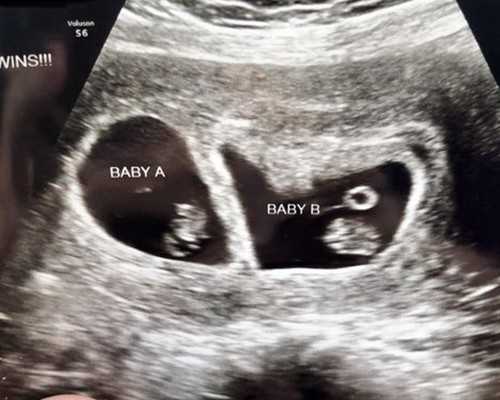

香港验血让朋友带过去_过程有惊无险对于这个即将到来的新生命,连周围人也都会被这个还未出生的小家伙感染上一种喜悦开心的心情,围绕着宝宝的相关问题更是孕妈们在闲聊时,必备的话题之一,备受瞩目的地方也当属这个小家伙的性别了。很多孕妈来香港做验血或是做无创的时候,由于人生地不熟,难免会有着许多担忧,比如我不认识路怎么办?我不懂粤语怎么办?香港的酒店怎么订啊?香港的大巴怎么坐啊?

B超检查虽能了解胎儿情况,但也不能太频繁1、B超的检测原理

B超的检测性别需要等到胎儿成型好,然后才能通过超声波然后来检测胎儿,根据不同性别的胎儿的外表是存在差异性的,所以超声波扫描出成型的胎儿外表判断性别。这也是为什么B超检测需要这么久的怀孕时长

香港验血为什么准确很多宝妈在从怀孕的那一刻起就对宝宝施加无尽的爱。尽自己所能的来呵护宝宝,而也正是因为对宝宝的关爱,很多宝妈都迫不及待的想尽早知道宝宝的性别,因此很多宝妈都选择给宝宝做性别鉴定在每个怀孕妈妈心中,知道肚子里孩子的性别肯定是一件开心的事,所以检测性别就是让怀孕妈妈更早的满足好奇心,好奇心满足还可以让怀孕妈妈们更早的准备孩子的许多用品。香港验血的准确性是可以得到全世界认可的,安全也可靠,准确率有99.8%。因为这是根据怀孕妈妈的血液中有胎儿的游离DNA片段,所以检测血液中DNA片段是不是有Y-DNA就行,准确率所以这么高。如果想达到这么高的准确率是有条件的,首先怀孕的时长一定要七周以上,当然不是越长越好,七周以后检测的结果准确性都差不多。七周怀孕妈妈的血液中胎儿的游离DNA片段越来越浓,会达到最高值。还有就是怀孕妈妈的胚芽需要达到十毫米,这些都可以再去香港验男女之前可以去医院做个B超。特别提醒一点在香港验血需要有B超的检测单,因为达到上面我说的条件才可以检测,以防影响准确性。关于检测Y染色体上的基因的方法,原来Y染色体上有一种被命名为"SRY"的基因,而这种基因只存在于通于Y染色体上,在X染色体上没有,所以通过染色,这种基因会与试剂发生特殊的颜色反应,所以通过观察,如果有颜色反应,那么就含有Y染色体,即宝宝是男孩,反之,则为女孩儿。两者的最终准确率对比:B超需要一定的条件才能做到比较高的准确率,需要检测医生的经验,还需要比较很正的的胎位,然后再利用超声波检测,把所以条件满足,准确率最高可以达到80%。但是大陆一般不允许检测性别。首先,宝妈一定要确保孕期达到了7周或者7周以上,并且在当地的医院检测出胚芽的长度达到10mm或者10mm以上。宝妈没有经历过重大输血以及器官移植等重大型手术。记得去港要携带充足的现金,虽然移动支付已经在大陆很普及,但是在香港很多地方不能使用,所以要提前准备好港币。通常检测的费用需要4000港币左右,但是您还有其他的消费,应该做到有备无患。